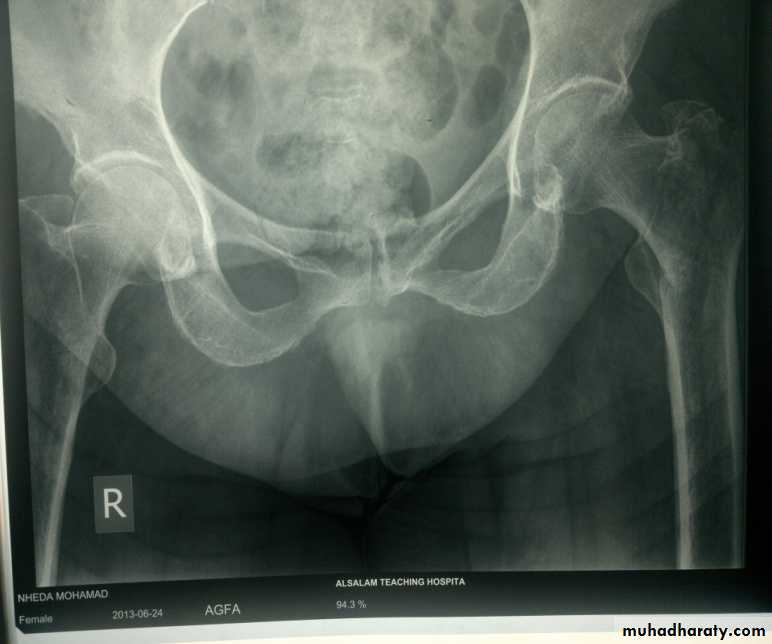

1- avascular necrosis of the femoral head ,appear in the x-ray as an increase in density of the femoral head , but it is not seen before 6 weeks and some time up to 2 years .In early weeks , bone scan and MRI will be helpful in the diagnosis of ischemia .

1- a vascular necrosis of the femoral head .

Early diagnosis by MRI

few weeks later we can diagnose it by bone scan .

X-ray changes may not show itself for months or even years.